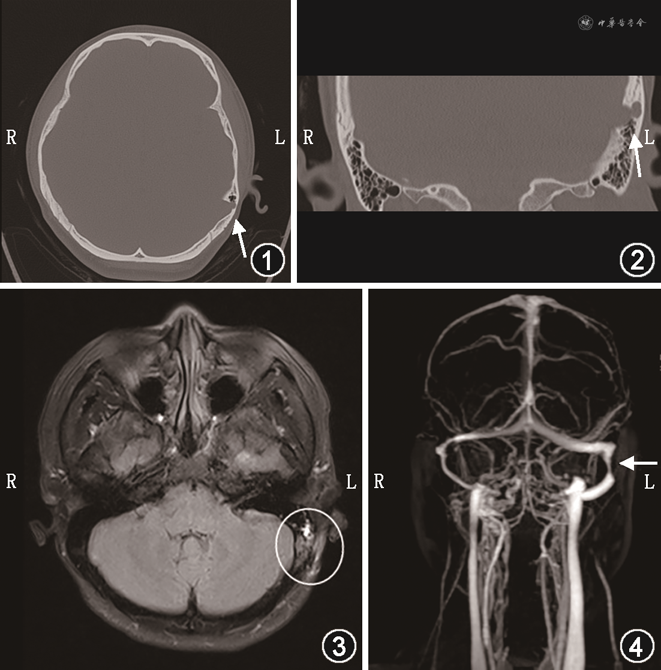

患者,女,24岁,因“左耳搏动性耳鸣2年余”于2021年1月19日就诊于浙江省立同德医院耳鼻咽喉科。患者入院前就诊于外院,颞骨MRI提示乙状窦憩室,患者拟行手术治疗就诊于我院。入院诊断:血管性耳鸣。完善术前检查:查体鼓膜完整、标志清晰,纯音测听无明显异常,压颈试验阳性。完善颞骨CT提示左侧乙状窦憩室(图1,2)。于2021年1月21日在全身麻醉下行乙状窦缩窄术。术中取耳后C形切口磨除部分乳突骨质,暴露乙状窦憩室,沿骨窗边缘钝性分离,切取少许颞肌经骨窗填塞于乙状窦沟骨壁深面,利用医用胶固定颞肌筋膜。术后患者清醒即诉耳鸣消失,术后第1天患者诉耳鸣消失,无耳闷、头痛、眩晕等。术后第2天患者无异常办理出院。患者术后半月内出现3次恶心呕吐伴视物波动感,出现右耳耳鸣,第1次为术后4 d,于乘飞机后出现,患者误认为是晕机,后患者出现恶心呕吐伴有低热,在当地以“上呼吸道感染”治疗未见改善,后患者出现视物波动感加重及视物模糊,就诊于外院眼科发现视乳头水肿。术后1个月,患者再次就诊于我院,眼科会诊:眼底镜提示视乳头水肿,神经外科会诊:颅高压,再次入院完善中耳MRI及头部血管造影(图3,4),入院诊断:颅高压,乙状窦缩窄术后,耳鸣。入院后予20%甘露醇250 ml(bid,静脉滴注),患者诉恶心呕吐好转,仍有右耳耳鸣,呈持续性。于2021年3月5日在全身麻醉下行手术治疗,行耳后切口,取出前次术中使用了医用胶水的颞肌筋膜,术中手术器械轻轻撬开填塞物,未发生填塞物与乙状窦粘连并导致乙状窦破损出血等情况。乙状窦形态大部分恢复。从术前CT上可以看出来,乳突部分去除骨质不多,乳突影响不大,受影响的乳突部分和术腔内填塞前次手术填塞用的一些骨皮质骨片,封闭术腔。术后第1天,患者诉双侧耳鸣消失。术后10个月回访,患者诉双耳耳鸣消失。